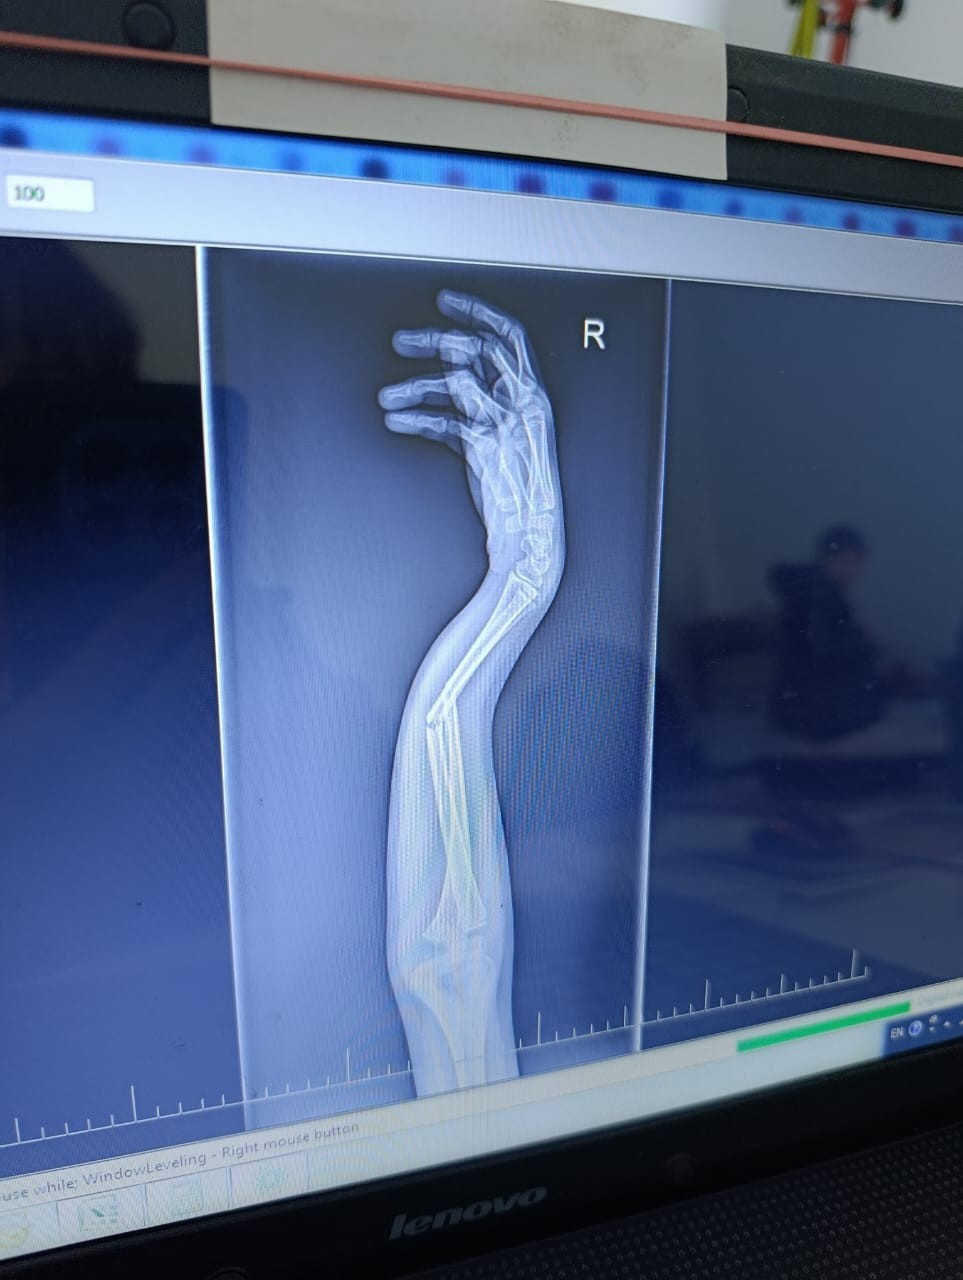

Здравствуйте, у сына, 10 лет, был перелом двух костей на правой руке. Одну кость вправили хорошо, другую на 50%. Врач говорит, что нет необходимости довправлять другую кость, но я переживаю и не понимаю как она может срастись. Сперва неделю ходил с лангетой, потом поставили гипс. Посмотрите пожалуйста снимки. Может ли кость нормально сростись или нужно настоять на операции, что бы вторую кость установили более ровно?